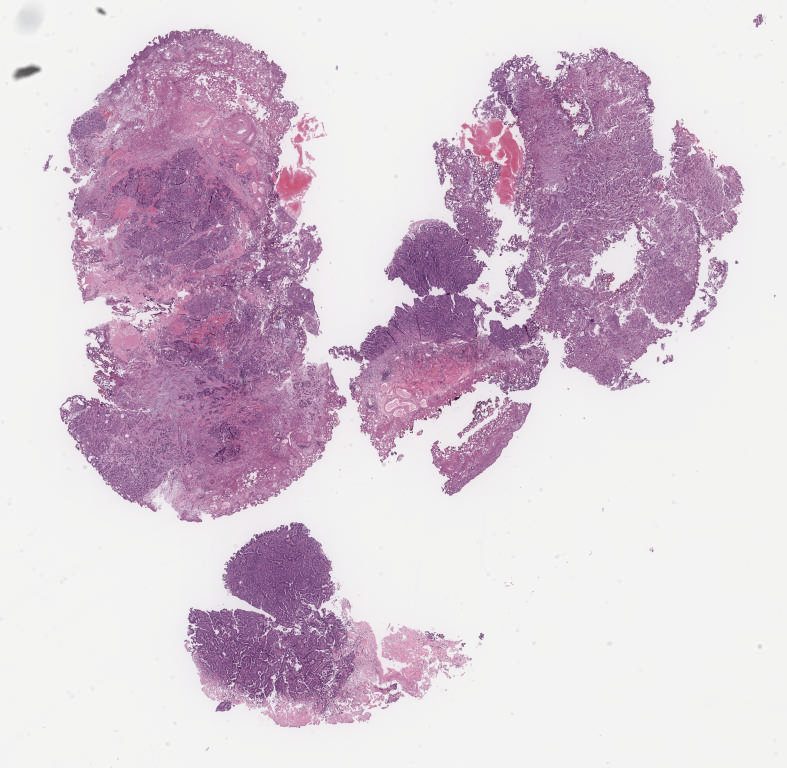

Case1.svs

85655

x

65821

@

40X